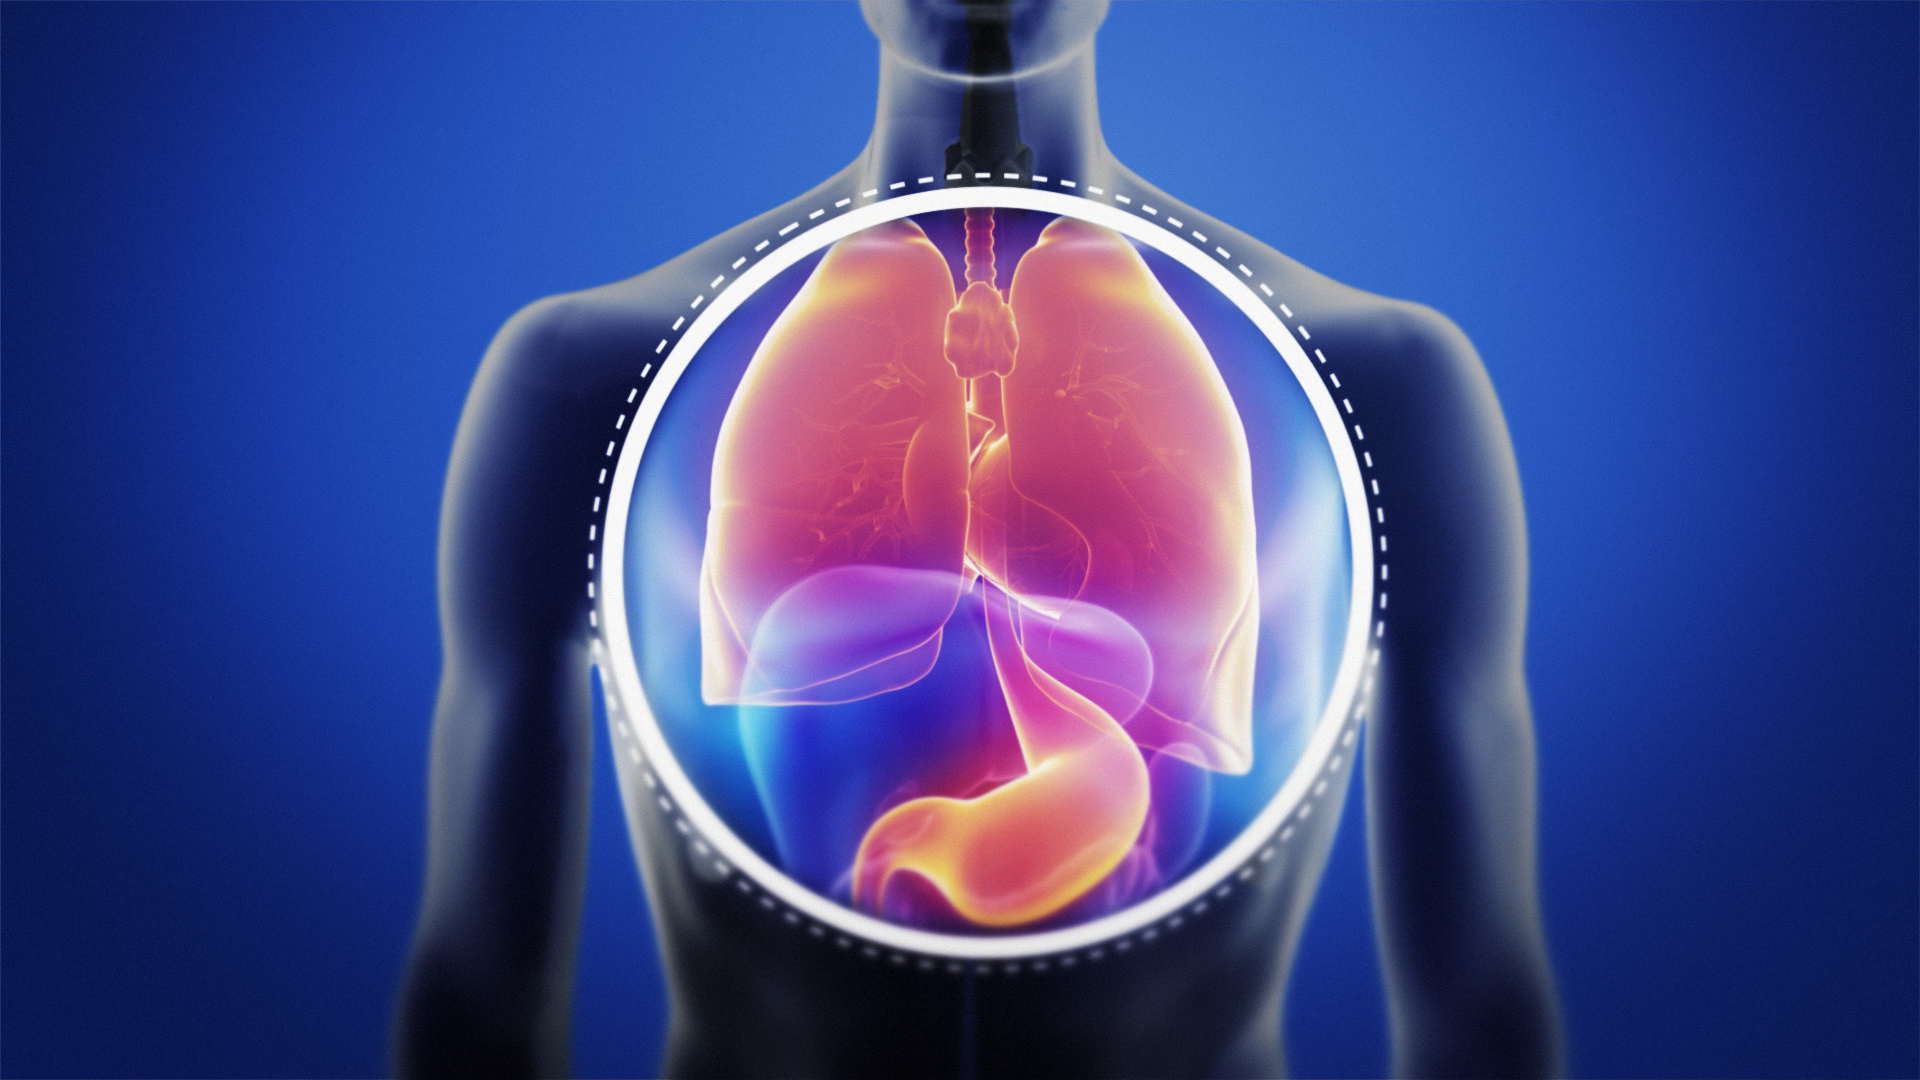

If it continues for a long period of time (is chronic), it can cause other more serious health effects. The acid can cause the oesophagus, throat, or voice box to become red, inflamed, and irritated. It even gets into the nasal passages in some people. With LPR, acid reflux makes its way even further up into your throat and voice box (larynx). It produces symptoms such as heartburn and nausea. That's acidic enough to damage strong materials such as teeth and bone. On the pH scale that measures acidity, strong alkali is 14, neutral water is 7, and stomach acid has a pH between 1 and 2. It can travel up the oesophagus (the tube leading from the throat down to the stomach). LPR is like gastro-oesophageal reflux disease (GORD), but it affects the throat and larynx (voice box).īoth LPR and GORD can happen when stomach acid escapes from the stomach. You could have laryngopharyngeal reflux (LPR).

You may have had allergy medications, cold and flu medications, or antibiotics, but the symptoms continue. Or asthma-like symptoms (chest tightness, wheezing, or difficulty breathing)? But you’re pretty sure you don’t have an allergy, cold, or any other respiratory condition? Do not smoke or let anyone else smoke around your child or in your house.Do you sometimes have a sore or itchy throat? Or excess mucus in your throat so you need to clear your throat often? Maybe a persistent cough, or a raspy voice.